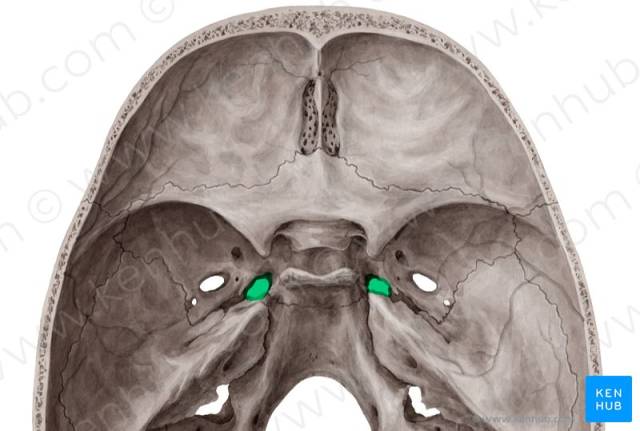

笔记第32期:颈内动脉岩段和破裂孔段解剖

1216x764 - 729KB - PNG

1456x684 - 1554KB - PNG

1096x748 - 476KB - PNG